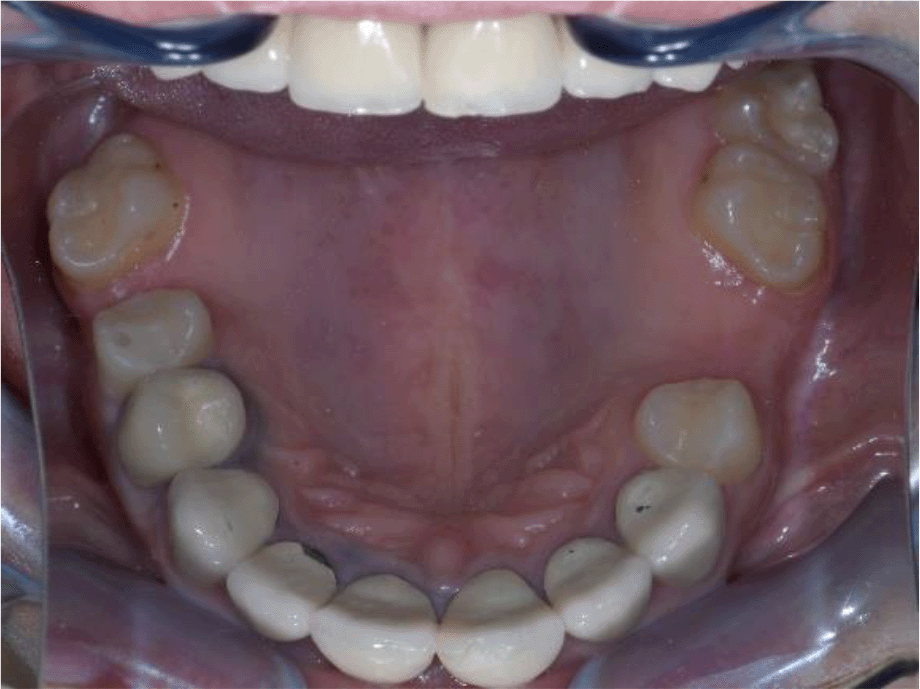

On the lower jaw, an advanced phase of abrasion (Attritio dentis cum abrasione) of the frontal teeth was established, reaching the dentin area. Defects of the dentitions were solved with ceramic restorations of 35, 36, 37 on the left and 45, 46 on the right. The occlusal plane was incorrect – the lower frontal teeth were higher. There was a deep overlap of the lower frontal teeth in central occlusion (Figures 3 and 4).

Figure 3. Abraded lower teeth and occlusal plane at initial presentation.